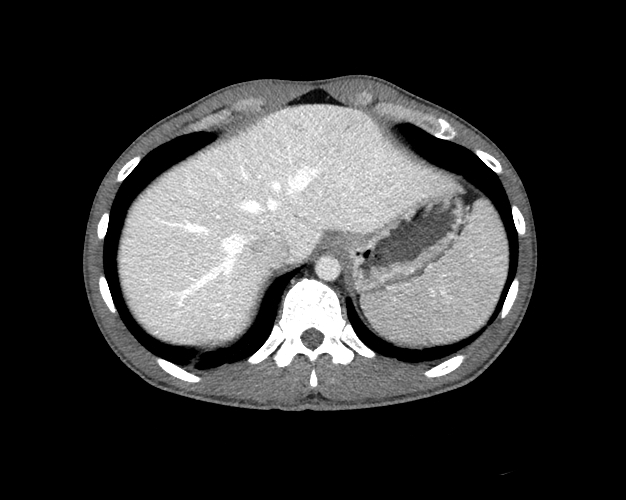

Body

Covers abdominal CT anatomy.